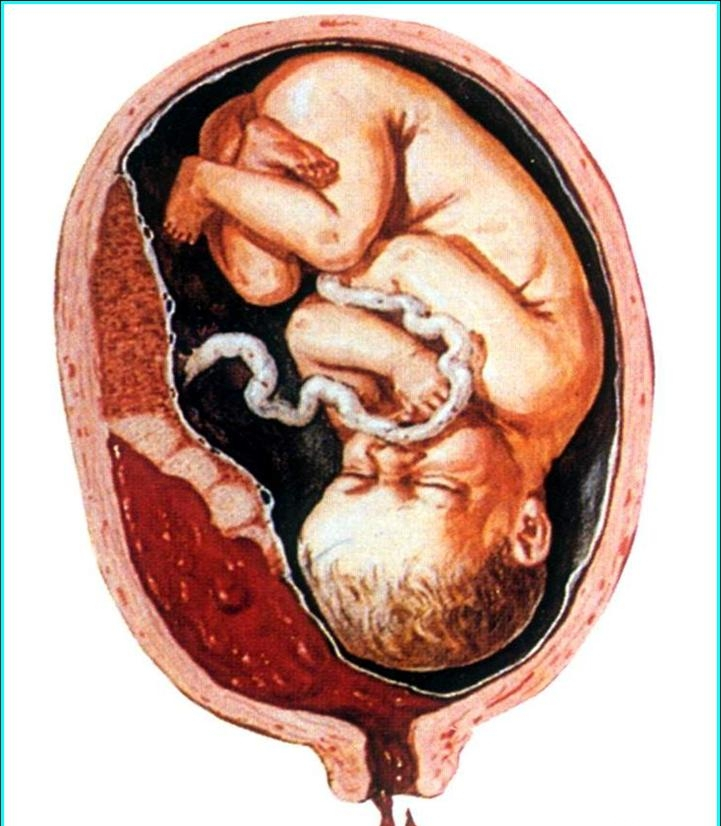

懷孕期間是如何胎盤早剝

胎盤早期剝離